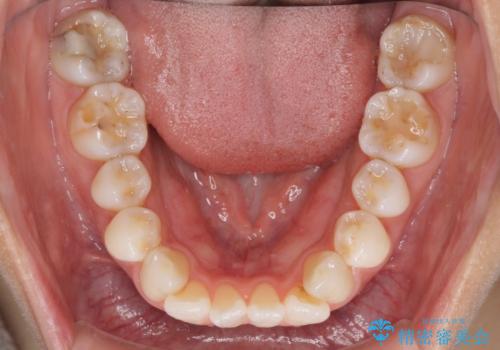

- 少しだけ前に飛び出ている前歯を気にして来院された患者様です。

上顎歯列全体を後方に移動させる必要があり、インビザライン単体での治療は困難と判断し、補助装置により左右側方歯列を移動させた後にインビザラインを用いることとしました。

インビザライン単独でも上顎歯列全体を後方移動することで臼歯の咬み合わせを改善できる場合もあります。しかしながら、矯正治療は当初設定したゴールに到達する必要があり、今回のような場合ではインビザライン単独では達成の可能性が低くなるので、補助装置を使用して、より確実に治療を行うこととしています。